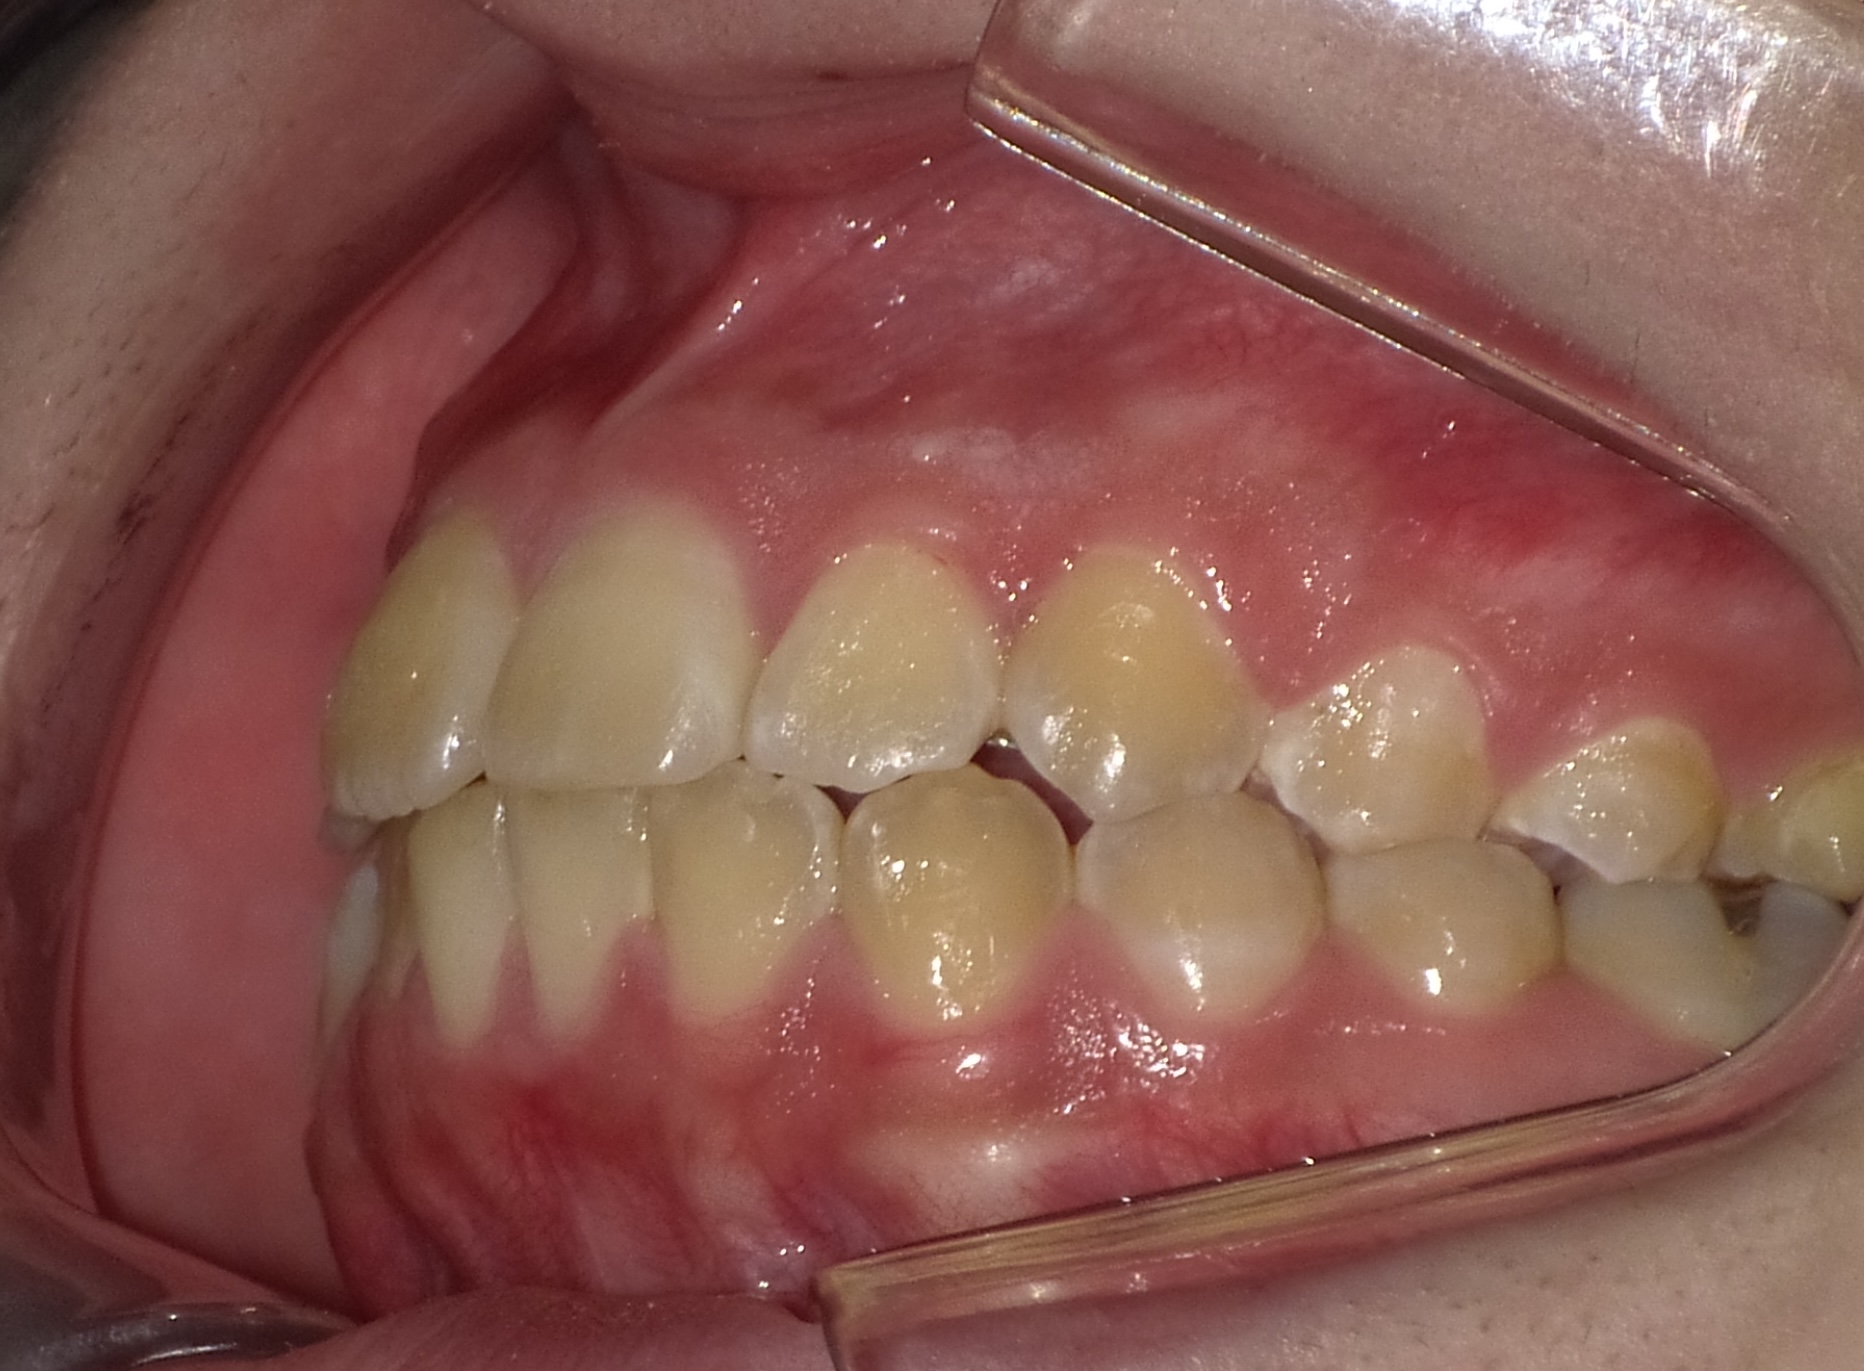

矯正後

| 症状 | 左上2番3番逆転症例 |